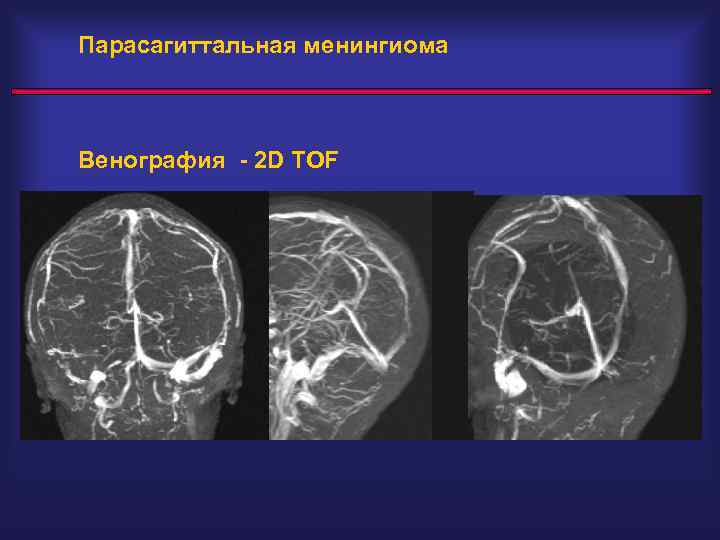

Парасагиттальная менингиома Венография - 2 D TOF